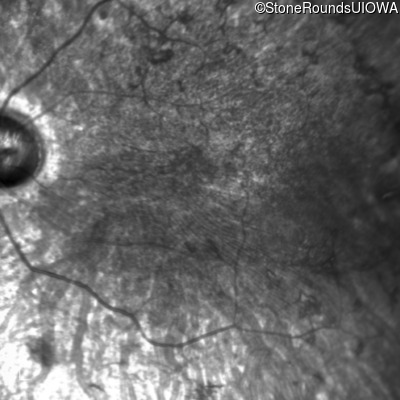

This 21 year old man first had difficulty seeing the blackboard in the 5th grade. Two years later he began having difficulty seeing in dim light. In high school he was approximately 50 pounds overweight, but was able to lose that weight with a strict diet.

| Bardet Biedl Syndrome | BBS1 | Met390Arg ATG>AGG | Arg277Lys AG(G)>AA(G) | AR |